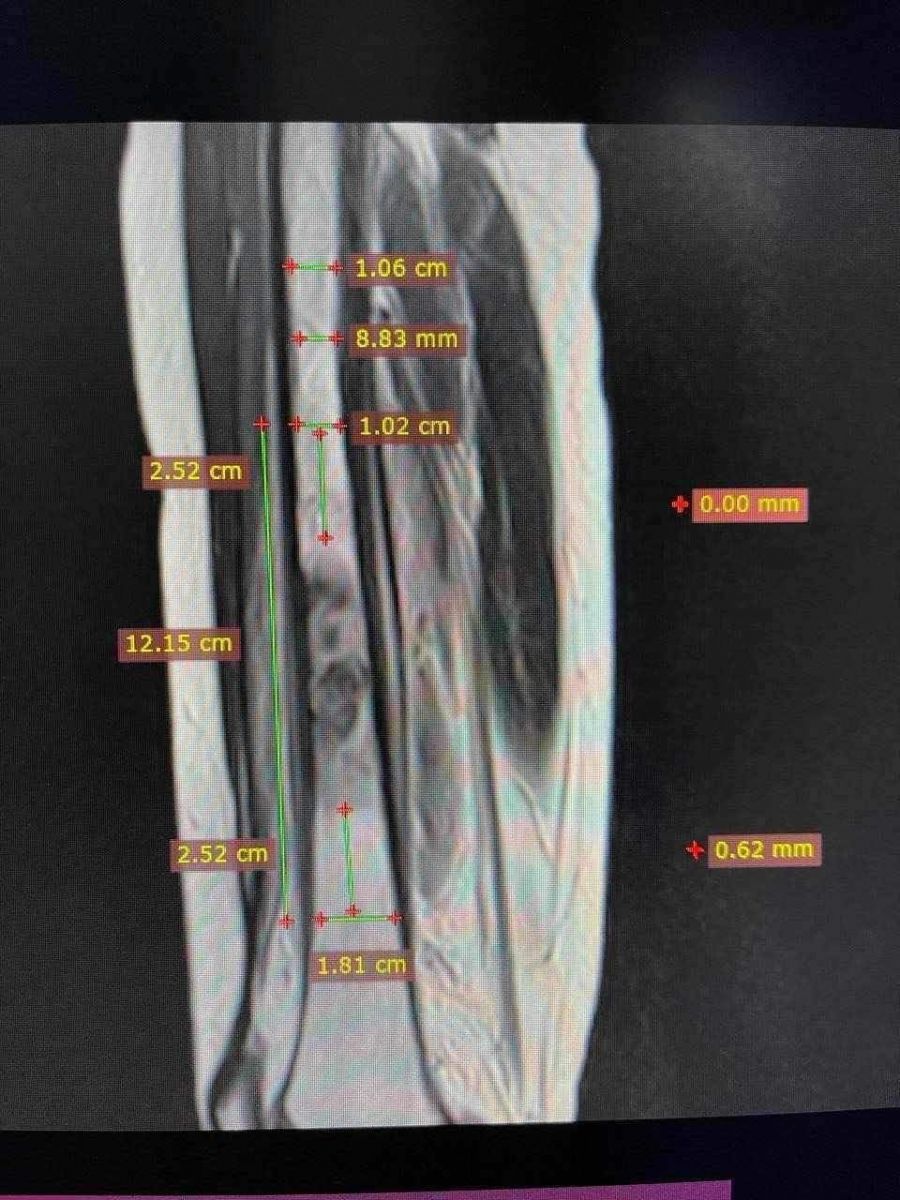

13 настай Н.Түвшинбат хүү Остосерком буюу дунд чөмөгний хүнд хэлбэрийн ясны хорт хавдар оноштойгоор 12 дугаар сараас эхлэн Турк улсад эмчилгээ хийлгэж байна. Хавдрын тархац бууруулах эмчилгээг таван сарын хугацаанд 300 орчим сая төгрөгөөр хийлгэсэн бөгөөд хавдар авах мэс засал энэ сарын 16-ны өдөр товлогдоод байсан юм.